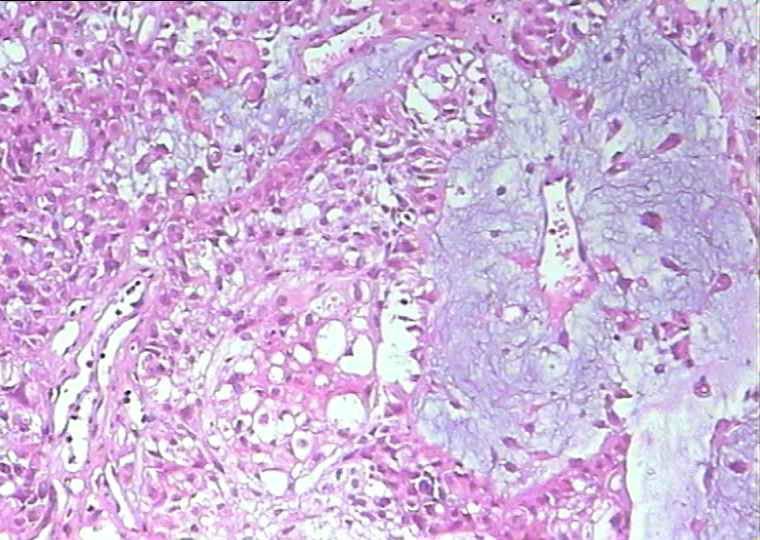

女,56岁

宫腔内淡黄色隆起型肿物数枚,实性质软,直径1.5~3cm,其一侵及浆膜面,肿物累及颈管及一侧输卵管,卵巢,并在输卵管膨大处形成直径0.5cm淡黄色菜花样肿物。